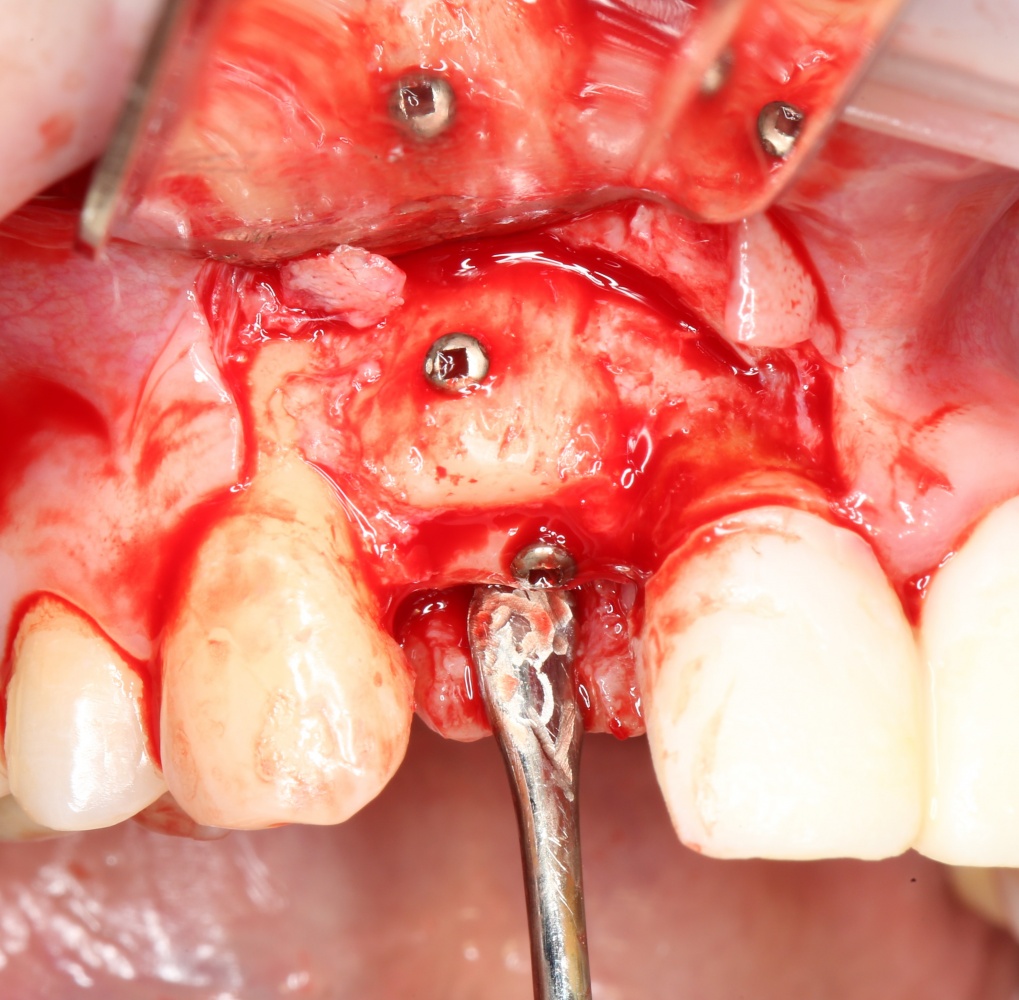

Глянем на то, что получилось:

Осталось адаптировать костный блок (убрать острые края), проверить его фиксацию и, при необходимости, добавить винты. Десятисекундное дело.

Изоляция области аутографта и имплантатов барьерной мембраной.

Перекрывать костный блок барьерной мембраной или оставить так? По этому вопросу есть много мнений. Между тем, в публикации по методике есть ясное показание, когда это требуется.

Конкретно в этом клиническом случае между костным аутотрансплантатом, ложем и имплантатами есть пустое пространство. Если его не изолировать от мягких тканей, они прорастут и осложнят интеграцию аутографта. Поэтому я решил перекрыть костный блок барьерной мембраной, пусть это делает хирургическую операцию немного дороже.